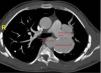

Case reportAt the age of 12, a young man had been accidentally shot in the anterior chest (4th-5th intercostal space), suffering spine injury that resulted in paraplegia. He retained functional autonomy in a wheelchair. At age 15 a mild cardiac murmur was detected during a routine consultation, but he had no cardiovascular symptoms. At the age of 25, although he was still asymptomatic, the murmur had worsened and become continuous, and he was referred for cardiological consultation. Chest X-ray during etiological study revealed a hypodensity in the left perihilar region. This finding was investigated by computed tomography (CT), which revealed a pseudoaneurysm, with fistulization to the left pulmonary artery (Figures 1–3).

The patient remained active and working, with no cardiac symptoms during outpatient follow-up. In 2007, at age 35, left ventricular dilatation and systolic dysfunction (ejection fraction 41%) were observed, probably due to high output caused by the fistula. The case was accordingly re-evaluated and it was decided to intervene. A 28 mm×100 mm Valiant Thoracic Stent Graft was implanted percutaneously; the procedure was uneventful. He continued to be monitored in cardiology follow-up consultations, which showed good cardiovascular evolution, with recovery of left ventricular function (ejection fraction stable at 53%).

Currently, at age 41 and six years after the procedure, he is well, with no cardiovascular symptoms (Figures 4 and 5).